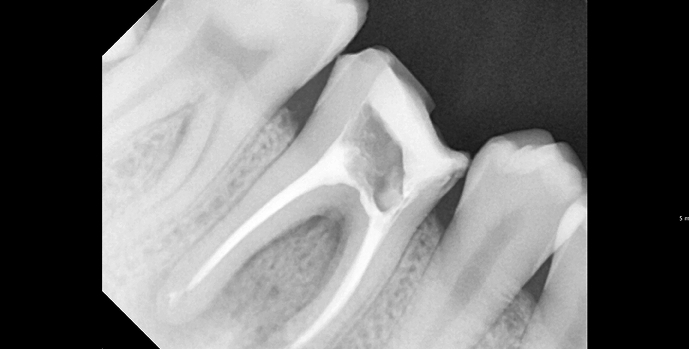

진단 및 영상검사

X-ray(필요 시 3D CT)로 염증 범위와 근관 형태를 확인하고, 통증 원인을 정밀 평가합니다.

BEFORE & AFTER

• 20대 남성 | 치근단병소 | 재신경치료 | 치료기간 4주

Before 2025.04.30

After 2025.05.29